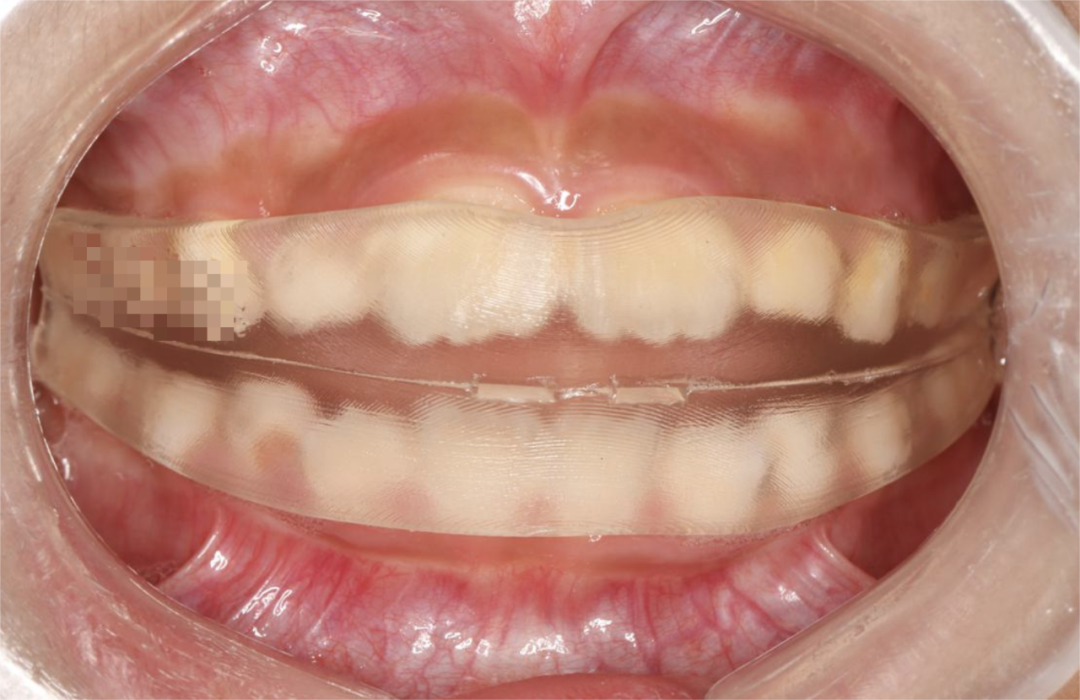

因为这个时期孩子的牙齿骨骼发育,还没有那么严重,比如说乳牙期的闭锁性深覆合,给孩子戴一种个性化定制的硅胶牙套,效果就会很明显。

那如果到了前牙2-2都换完了,也就是八、九岁的时候,这个时候戴个性化硅胶矫治器也有效,或者可以戴固定的矫治器、无托槽隐形矫治器,专门对牙齿进行压低后牙的控制。

那至于说工具,比如说我们做早期矫治戴个性化定制的硅胶类牙套,或者是做无托槽矫治器,我觉得这些都很好。

我现在认为无托槽矫治器对于解决内倾型深覆合,不管是儿童也好还是成人也好都是有效的。由于它对整个牙冠有很好的包裹性,这样对牙齿转矩控制也会很好。